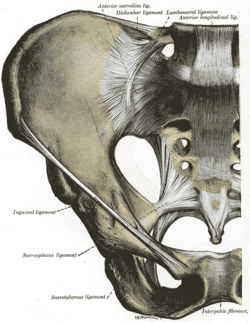

Articulations of pelvis. Anterior view.